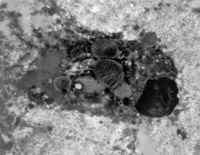

入院后立即用MEBO外涂保护创面,并行耕耘减张处理。伤后48h部分创面开始液化,伤后4天创面坏死组织已全部开始液化(图5-3-3)。每3~4h清除创面液化物一次并外涂MEBO。

原位切取创面组织病理切片检查,见坏死上皮组织间有大量颗粒样组织,新生上皮细胞和胶原纤维组织呈团样增生,并可见到典型的类似于胎儿皮肤结构的皮肤胚胎基(embryonic base,EB)(图5-3-4a,5-3-4b)。MEBT治疗10天后,在创面边缘取上皮组织病理切片可见到较原始的上皮组织。

5-3-3 伤后4天,创面在MEBO作用下进入液化期,创面皮肤组织开始再生

5-3-4a 新生上皮组织和胶原纤维增生,可见典型EB(皮肤胚胎基) HE×40

5-3-4b 新生上皮组织中可见微血管,胶原纤维和上皮细胞(干细胞)形成的皮肤胚胎基组织 HE×40